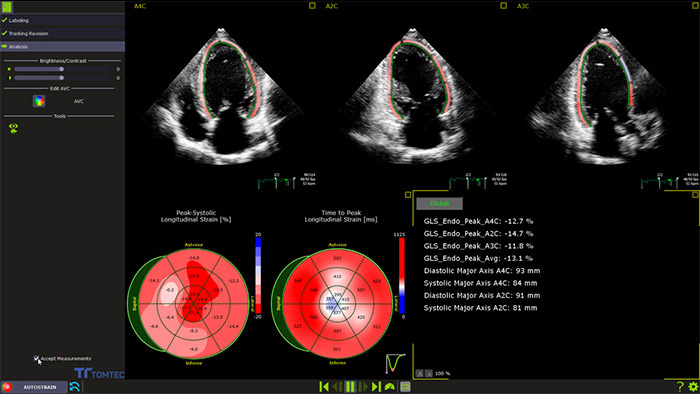

En tant que cardiologue, vous devez poser des diagnostics de façon rapide, sûre et reproductible. La nouvelle solution Philips Affiniti CVx, associe l’expérience de Philips dans le domaine de la cardiologie et l’expertise éprouvée de TOMTEC en matière de quantification.

Le nouvel Affiniti CVx intégre de nombreux outils TOMTEC de quantification automatisée sur lesquels vous appuyer: 3D Auto MV, 3D Auto LAA et AutoStrain LV. Ces outils vous offrent des mesures fiables et reproductibles nécessaires à différentes étapes de la prise en charge de vos patients.